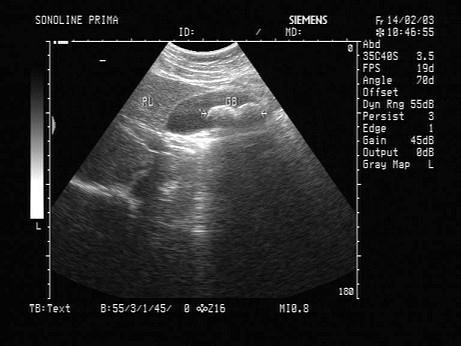

问题 男,46岁,上腹经常疼痛不适十多年,加重2天。声像图如图所示,诊断为?(?)

选项 A.胆囊蛔虫 B.胆囊多发性腺瘤 C.胆囊多发性结石 D.胆囊胆汁淤积 E.胆囊多发息肉

答案 C